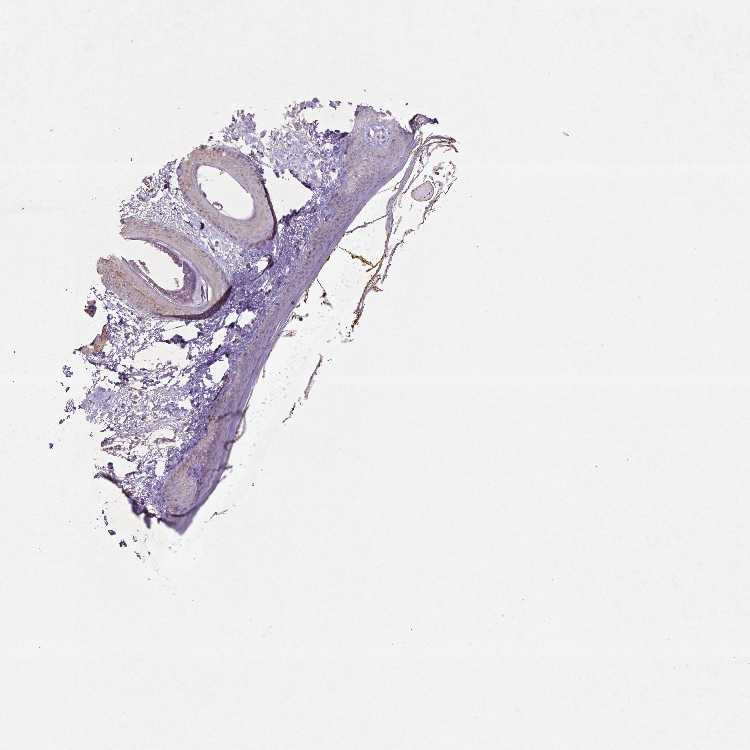

SKIN 2 - Antibody stainingi

Antibody staining in the annotated cell types in the current human tissue is reported as not detected, low, medium, or high, based on conventional immunohistochemistry profiling in selected tissues. This score is based on the combination of the staining intensity and fraction of stained cells.

Each image is clickable and will lead to virtual microscopy that enables deeper exploration of all samples and also displays staining intensity scores, fraction scores and subcellular localization as well as patient and tissue information for each sample.

Antibody CAB069425Antibody CAB080053Antibody CAB080065Antibody CAB080070Antibody CAB080081Antibody CAB080095Antibody CAB080097

Epidermal cells MediumMediumNot detectedLowNot detectedMediumMedium